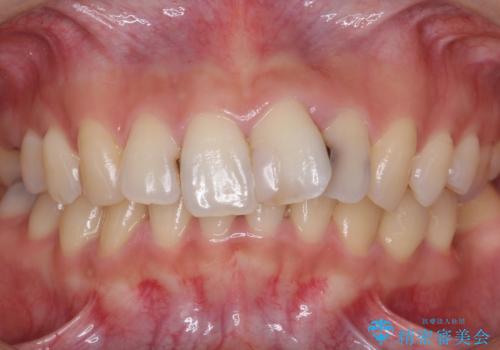

- 前歯をきれいにしたいとのご希望により来院された患者様です。

ご希望により、上の前歯4本のセラミッククラウンによる補綴治療を行いました。

- ¥572,000 (根管治療×1本、土台×1本、仮歯×4本、クラウン×4本) ※税込費用は治療当時の料金となります

- 天然歯を削ります

- 硬い素材は天然歯を傷つけてしまう場合があります

- かみ合わせや歯ぎしりが強すぎる方はセラミックが割れてしまう可能性があります